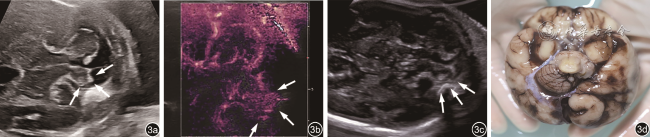

1. 产前超声检查:与正常胎儿小脑图像比较(图1),6例胎儿小脑横切面声像图示小脑形态均失常,左右不对称,一侧小脑减小,形态失常,伴或不伴蚓部异常,对侧小脑半球大小、形态正常(图23);其中4例小脑蚓部发育不全或发育不良,1例合并蛛网膜囊肿,1例合并神经元移行障碍和胼胝体发育不全。产前超声诊断:左侧小脑发育不全4例,右侧小脑发育不全2例。

图2 孕22周胎儿(例6)产前颅脑二维超声声像图。小脑横切面声像图示小脑形态失常,右侧小脑半球明显变小;小脑蚓部正常

图3 孕25周胎儿(例5)产前小脑二维超声声像图及产后脑部解剖图。图a小脑横切面声像图示左侧小脑半球明显变小,蚓部显示不清;图b能量多普勒显示左侧小脑半球小而血供较差(箭头所示);图c产后超声声像图示残存的左侧小脑半球实质(箭头所示);图d产后解剖图(颅底观)示左侧小脑下部几乎缺如

2. 微血流显像检查2例,发育不全侧小脑上动脉均不显示,对侧小脑上动脉可显示(图45)。

此外,超声还可在一定程度上观察到小脑半球的血供情况。Leibovitz等16通过后颅窝高分辨率多普勒超声观察了7例UCH胎儿,显示部分胎儿存在小脑供血动脉异常如小脑下后动脉缺失等。本院产前诊断的6例UCH胎儿中2例亦通过产前超声Micro F显微血流技术显示出双侧小脑半球血流不对称,一侧大脑后动脉及小脑上动脉走行可清晰显示,而发育不全侧仅显示大脑后动脉,小脑上动脉血流不显示。

微血流显像是一种新的超声血管成像技术,具有高灵敏度、高分辨率检测低速血流的特点,相较于彩色多普勒,微血流显像更易检出血流速度较低的微血管19,既往多运用于甲状腺、乳腺、肝等肿瘤疾病的诊断。现首次将微血流显像技术用于观察胎儿小脑的血管,从解剖角度看,小脑上动脉起自基底动脉,沿着小脑与脑干之间由后外向内前行的过程中逐渐发出小脑支和脑干支并布于小脑上面和中脑、脑桥背面20,而大脑后动脉与小脑上动脉伴行且呈平行走向,绕大脑脚向后走行。在小脑横切面微血流显像中,大脑后动脉和小脑上动脉显示呈平行走向的关系,因此,通过大脑后动脉可以判断小脑上动脉的位置及缺失与否,起到一定的辅助诊断作用。但此方法的不足在于目前仅通过小脑横切面对小脑幕面的小脑上动脉显示,其余小脑动脉的显示情况有待进一步研究。